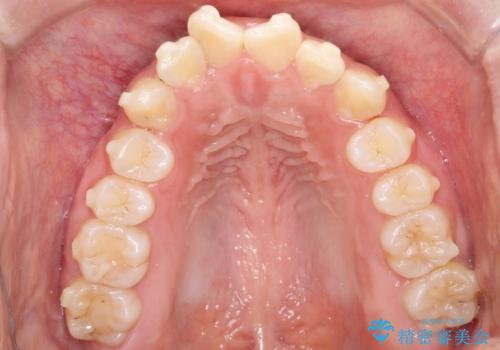

- 歯のデコボコ(叢生)を気にされて来院されました。精密な検査の結果、中等度の叢生と診断。患者様のご希望に合わせ、透明で目立ちにくい**インビザライン(マウスピース矯正)**による治療計画を立案しました。歯を抜かずに、歯列弓(歯が並ぶアーチ)を少しずつ拡大することで、歯が並ぶスペースを確保し、叢生を改善することを目指します。

今回の矯正治療では、透明なマウスピース型の装置インビザラインを使用しました。この装置は目立ちにくく、取り外しが可能なため、食事や歯磨きも普段通りに行えます。治療は、緻密に計算された治療計画に基づき、段階的に作製されたマウスピースを交換していくことで、歯列弓全体を徐々に広げていきました。この歯列弓の拡大により、不足していたスペースを確保し、歯のデコボコを効果的に解消。抜歯することなく、整った美しい歯並びと良好な咬み合わせを獲得していただけました。